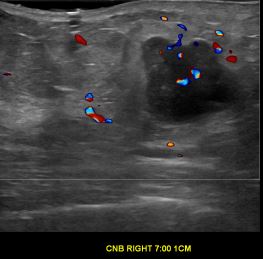

상기환자는 우측 유방 멍우리 만져져서  내원하신 70대 중반

여성분으로 의심스러운 우측유방혹 조직검사 시행해 유방암으로 진단되었습니다